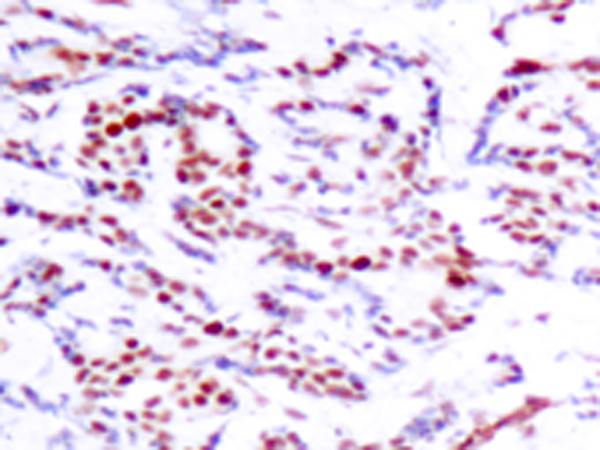

IHC positive control: |

Human breast carcinoma |

IHC Recommend dilution: |

50-100 |